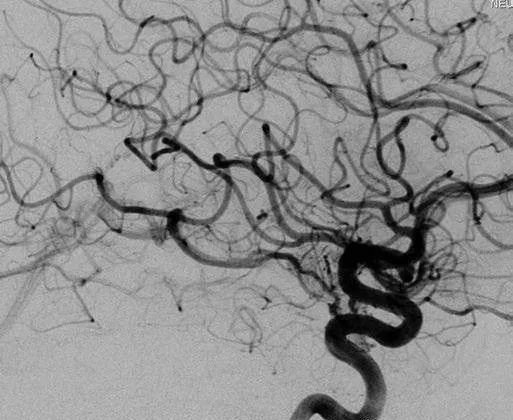

▼该AVM由ACA/PcaA分支、ACoA穿支和mPChA供血[右侧ICA造影

▼(a)侧位s(b)前斜位